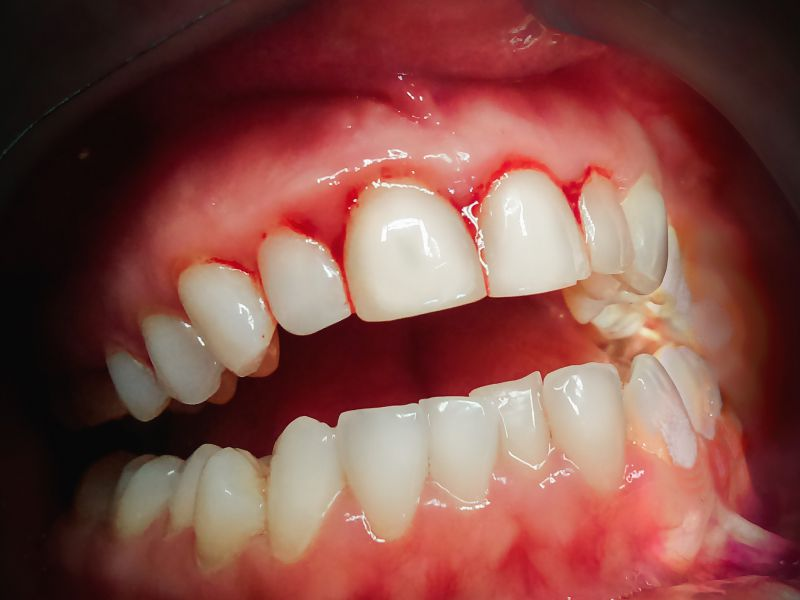

牙齿问题是特别多人都面临的困扰。牙疼起来真的是“要命”,不仅影响正常的饮食和睡眠,还可能引发其他健康问题。而且,牙齿不美观也会让人在社交场合中缺乏自信。许多人在选择口腔门诊部时,会担心医生不够专精,治疗成效不佳,甚至还会担心费用不透明。这些担忧让患者在就诊时充满了焦虑。

成都新都麦牙口腔门诊部拥有一支专精的医生团队。这些医生都具备丰富的临床经验和专精知识,他们经过严格的培训和考核,能够正确诊断各种牙齿问题,并制定个性化的治疗方案。无论是常见的龋齿、牙周炎,还是复杂的牙齿矫正、种植牙手术,医生们都能游刃有余地处理。